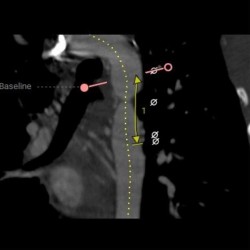

An aortic aneurysm is a dilation of part of the aorta in the chest. It is the largest artery in the human body, starting from the heart, it crosses the thorax, then descends to the abdomen, where it branches to supply the lower limbs. If an aneurysm is detected in this area, the only treatment is open surgery, performed under general anesthesia. Following the medical intervention in aortic surgery Tunisia, the patient must stay in the clinic for a minimum period of 4 to 7 days.

Open surgery is the reference method for treating any pathology of the aortic arch. In the elderly, aortic anomalies commonly appear: